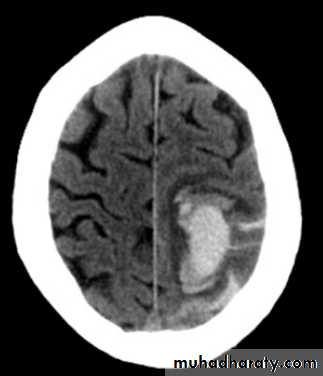

Acute Intra cerebral hematoma

CT finding :Hyper dense area , surrounded by edema , any where within the brain parenchyma.

Shifting of the midline

Compression of the ipsi lateral ventricle .

Associated with infarction , # , trauma concussion , tumor …..